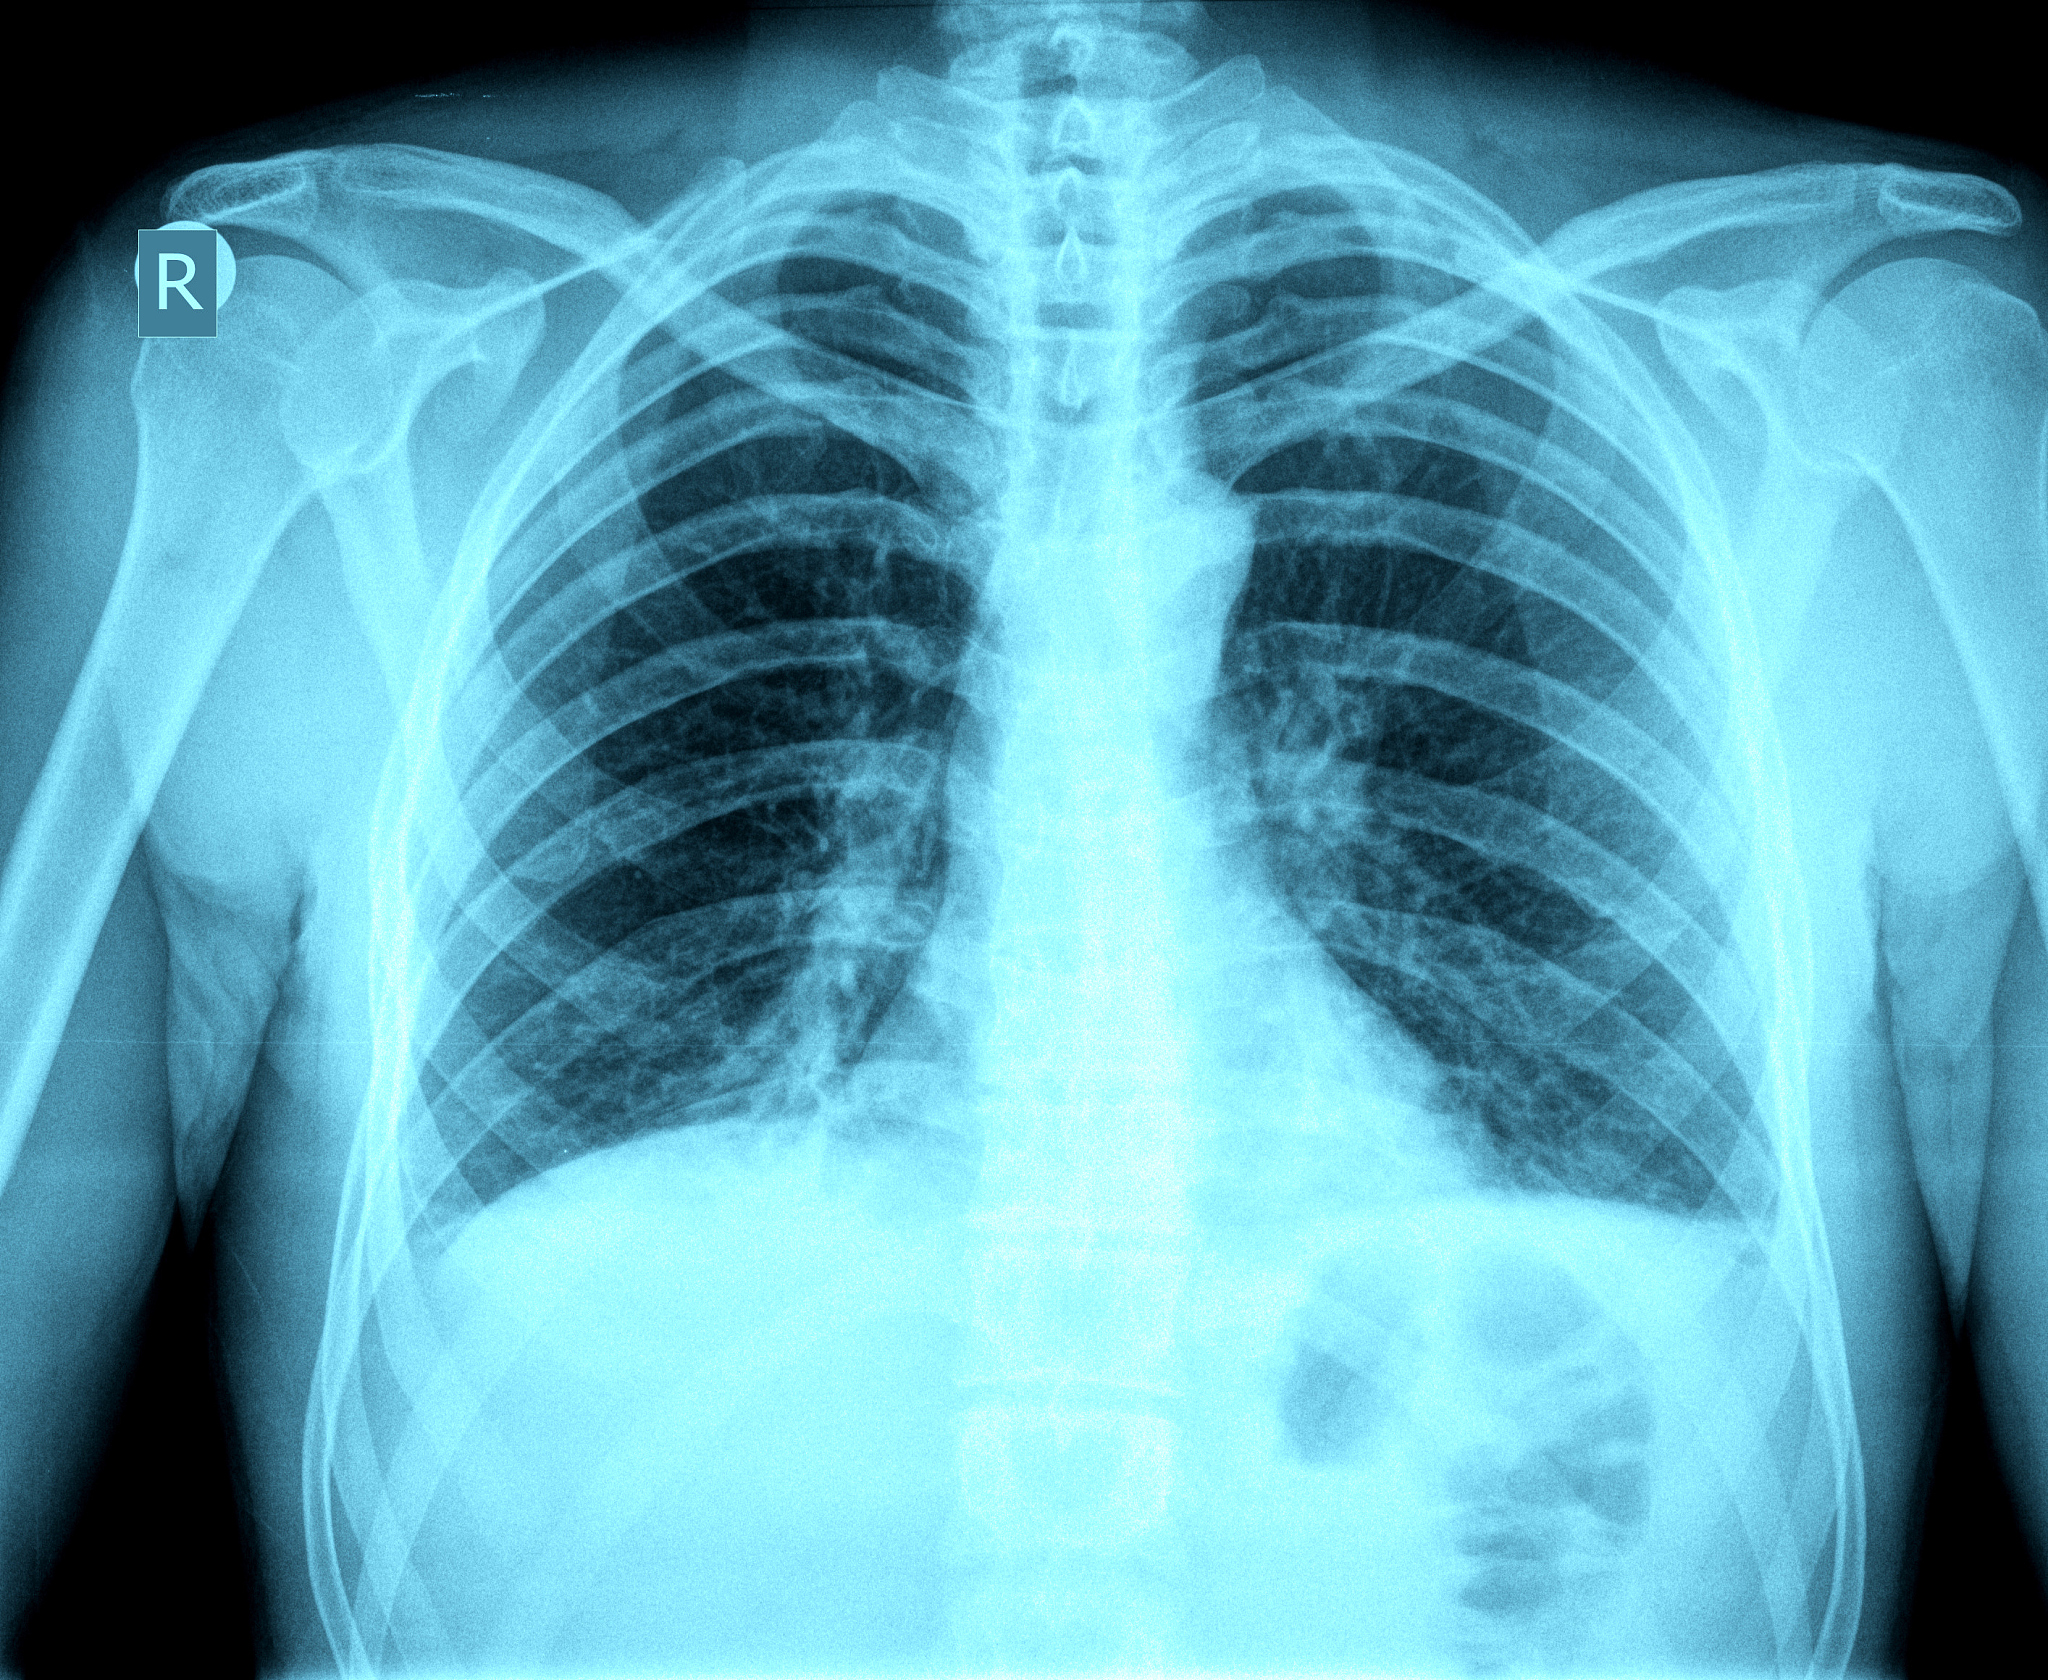

医学影像技术是医学领域中的一个重要分支,它通过各种医学影像设备,如CT、MRI、超声、X线等,对人体进行非侵入性或微创性检查,获取人体内部的图像信息,为医生的诊断和治疗提供重要的依据。医学影像技术专业的学生需要掌握医学影像设备的基本原理和操作技能,熟悉各种医学影像技术的优缺点和适应症,能够根据医生的要求进行影像检查和诊断。

在医学影像技术专业中,学生需要学习各种医学影像设备的基本原理和操作技能,如CT、MRI、超声、X线等。此外,学生还需要了解医学影像技术的优缺点和适应症,能够根据医生的要求进行影像检查和诊断。医学影像技术专业的学生还需要具备一定的计算机技术和电子技术的知识,能够熟练地使用计算机软件进行影像处理和分析。